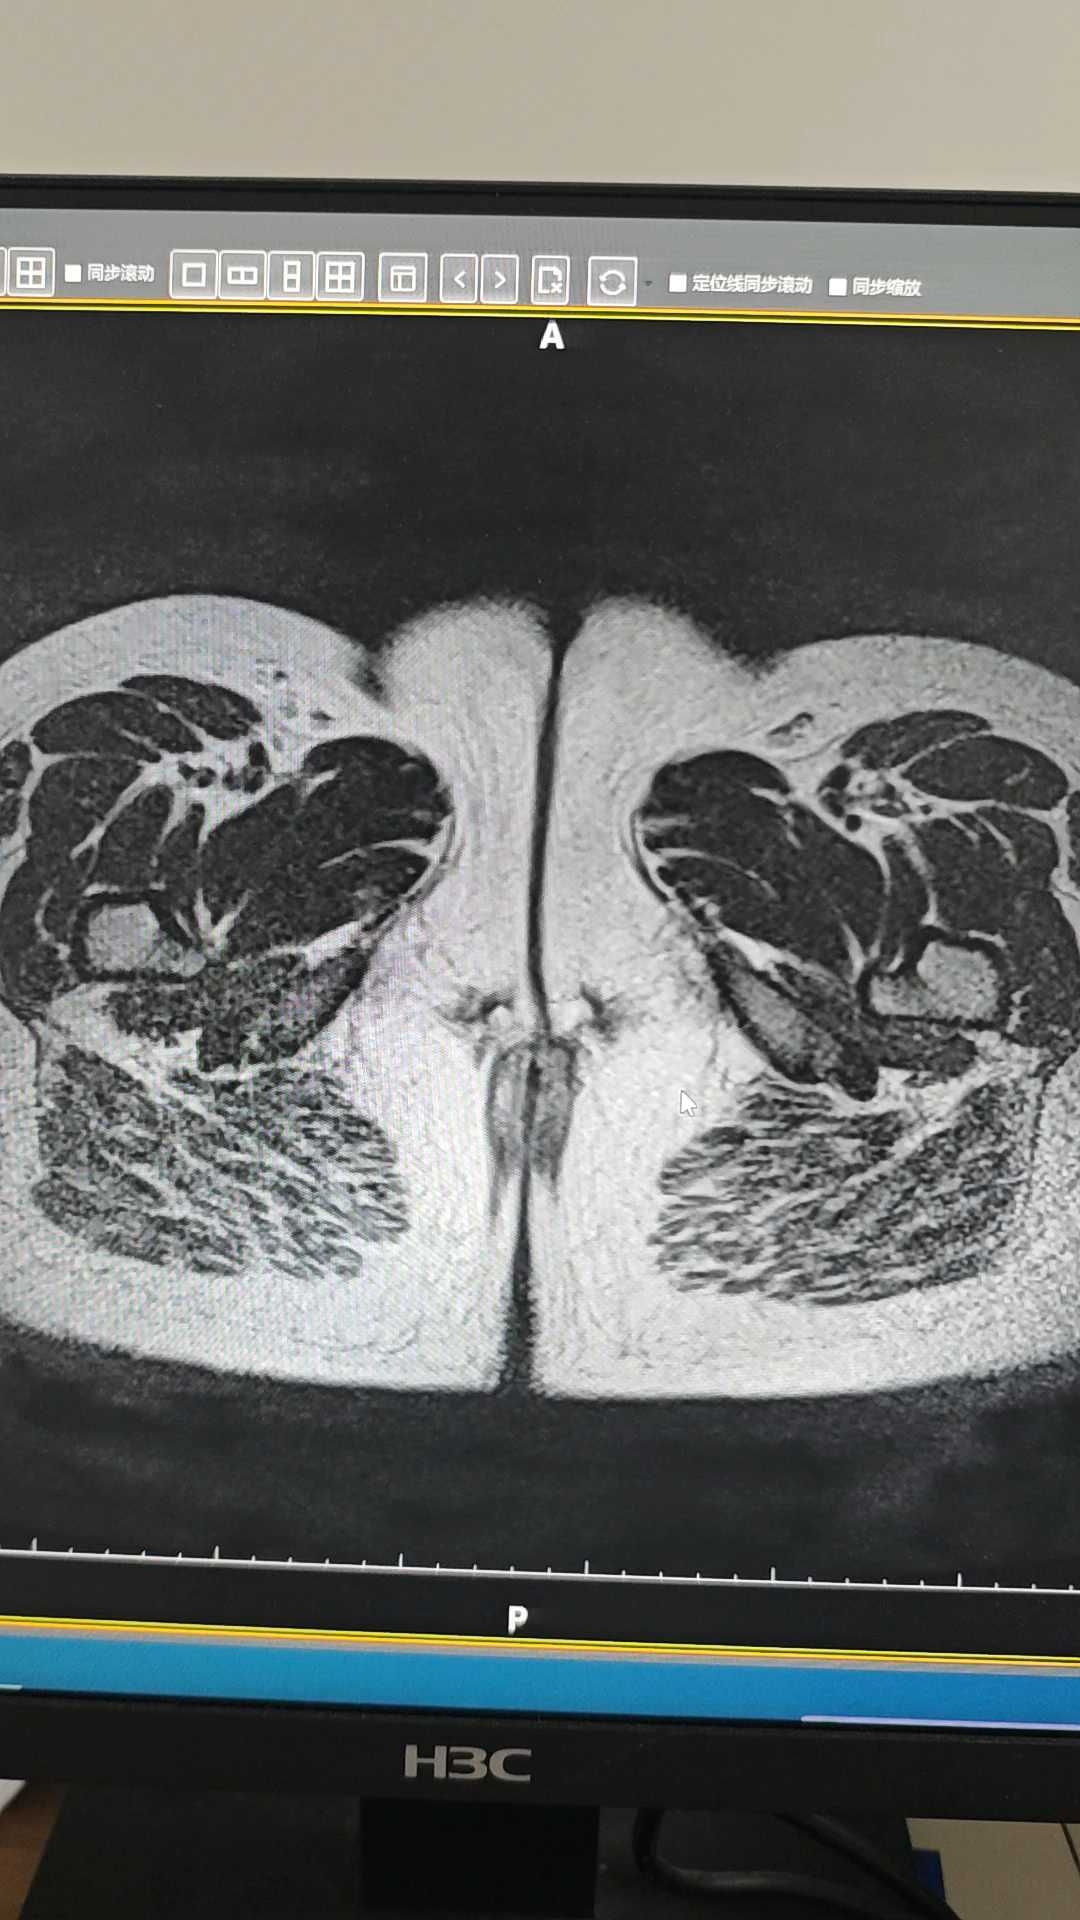

患者,女,13岁5个月,下腹痛4天入院。11岁初潮,月经不规律,量中,无痛经,末次月经2025.5.19。4.25首次出现下腹痛,在诊所输液治疗一天好转。5.31再次出现下腹痛,6.1外院检查子宫附件未见明显异常,血hcg正常。6.2诊所输液无好转。6.3入我院。查体:生命体征平稳,身高170cm,体重:80kg,下腹部压痛明显,腹肌稍紧,无反弹痛。妇科检查:外阴发育正常,未婚产式,肛腹诊检查不满意。盆腔彩超示:盆腔巨大占位性病变伴渗出,考虑来源附件良性囊性病变。盆腔MRI示:盆腔良性囊性病灶。女性肿瘤五项正常。考虑卵巢囊肿蒂扭转,急诊腹腔镜探查,术中见左附件扭转两圈,左侧输卵管囊肿大小约130*80mm呈紫黑色,左卵巢增大55*35mm紫黑色,行左附件切除术。

大家观察正常卵巢和缺血坏死卵巢MRI图像表现